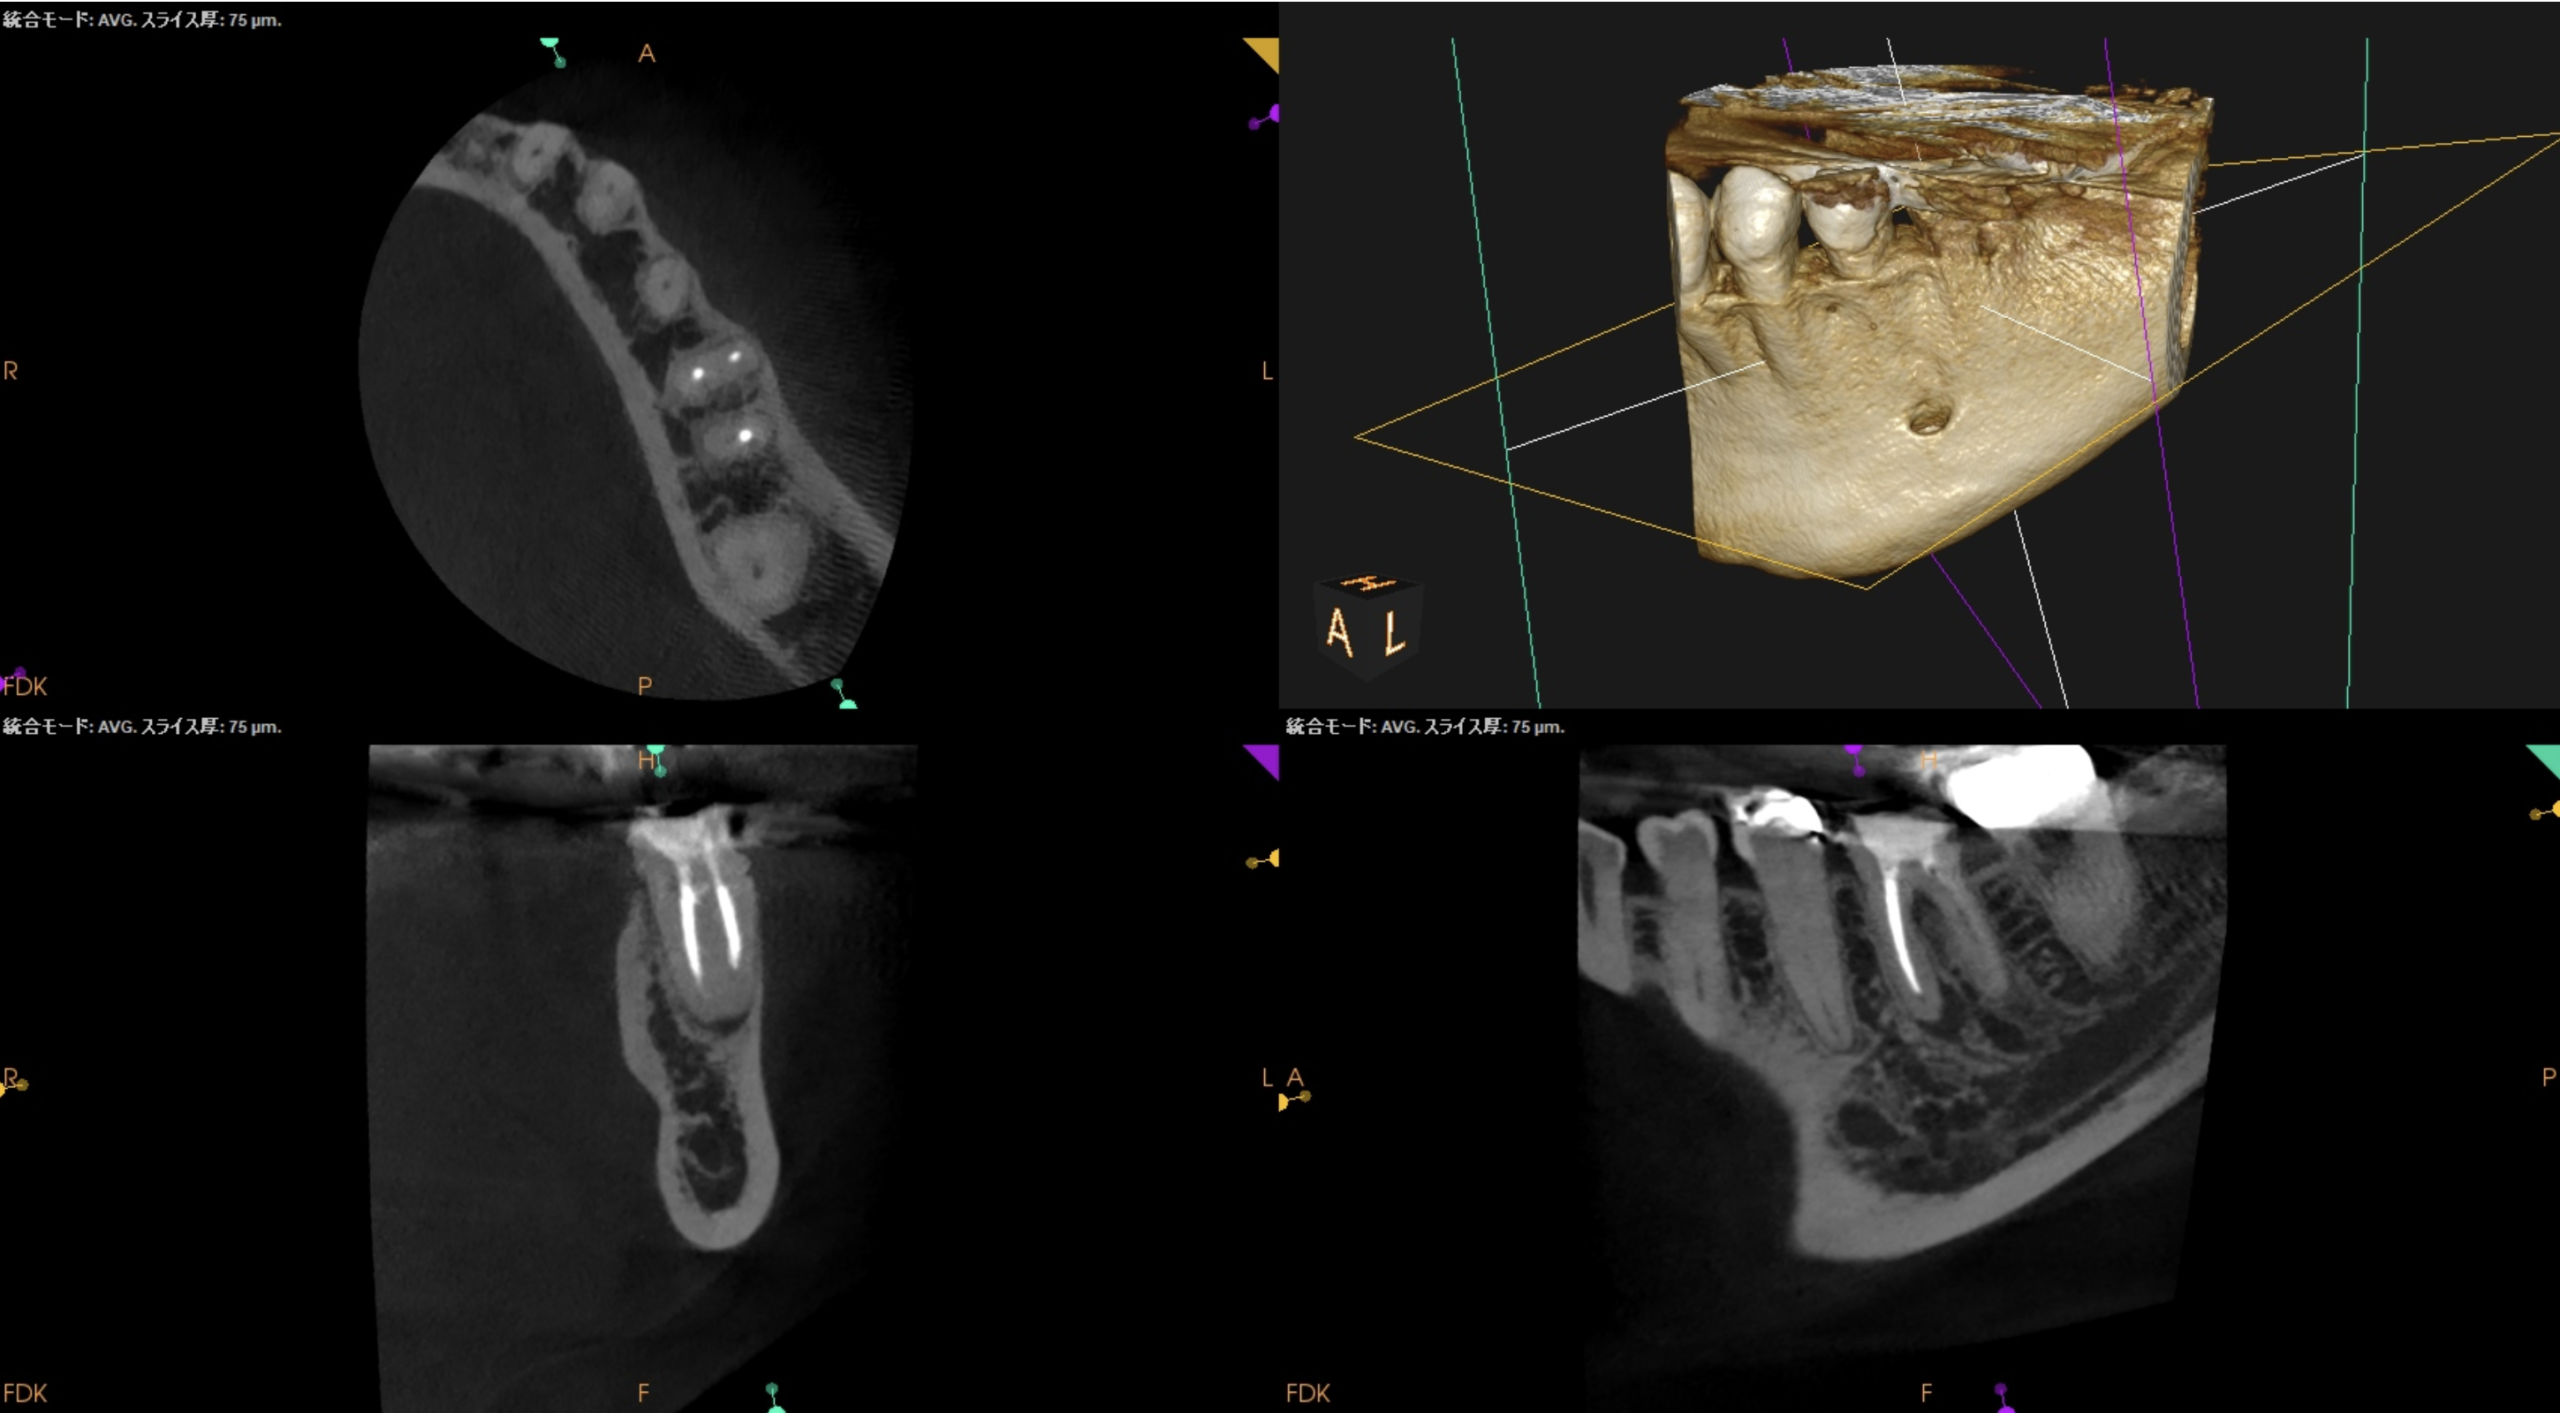

CBCTも撮影した。

CBCT(2025.10.31)

#19

MB

ML

D

ということで臨在歯の#18もCBCTを精査した。

#18

M

#18 Mのこの絵は縁下カリエスの可能性を示唆している。